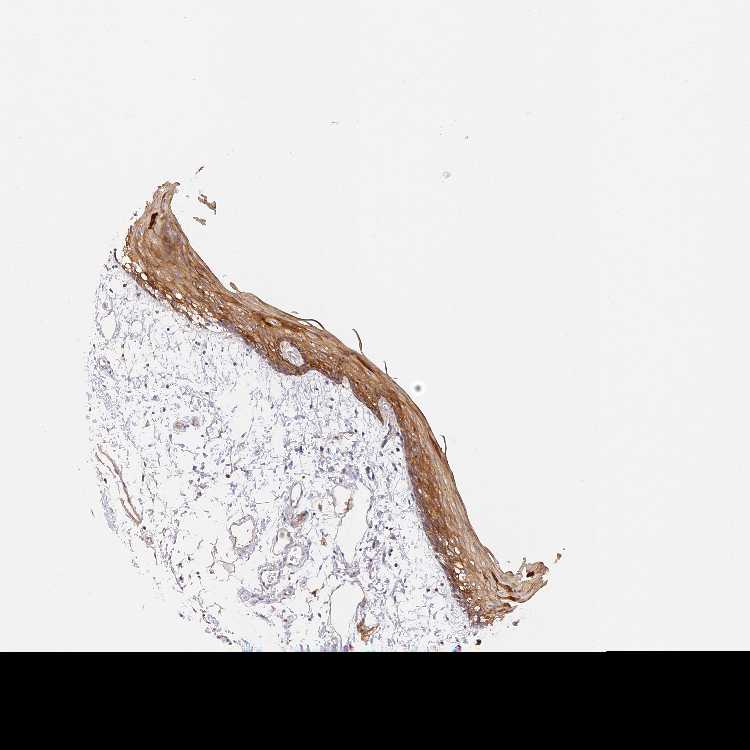

TISSUE PRIMARY DATA ORAL MUCOSA Show tissue menu

ORAL MUCOSA - Antibody stainingi

Antibody staining in the annotated cell types in the current human tissue is reported as not detected, low, medium, or high, based on conventional immunohistochemistry profiling in selected tissues. This score is based on the combination of the staining intensity and fraction of stained cells.

Each image is clickable and will lead to virtual microscopy that enables deeper exploration of all samples and also displays staining intensity scores, fraction scores and subcellular localization as well as patient and tissue information for each sample.

Antibody HPA044465

Squamous epithelial cells Medium